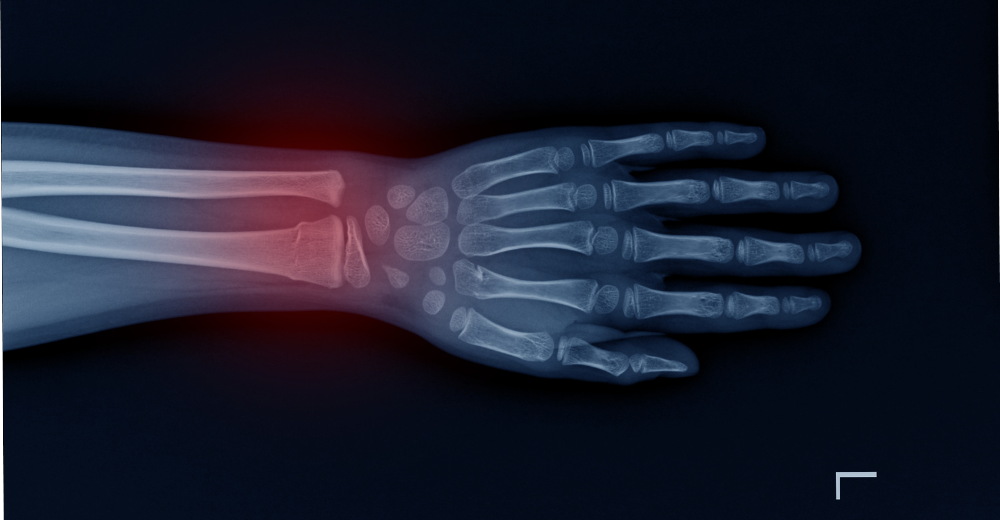

L’esame RX Polso è uno strumento fondamentale per diagnosticare patologie del polso quali fratture, distorsioni, lussazioni, artrite e altre condizioni che possono compromettere la funzionalità dell’articolazione. Al Poliambulatorio S-Medical Group di Sora, grazie alla precisione dell’esame e alla professionalità del team, è possibile stabilire un percorso terapeutico mirato per ogni paziente, garantendo diagnosi tempestive e trattamenti efficaci.

L’RX Polso è indicato in presenza di dolore persistente, gonfiore, limitazioni di movimento o dopo traumi che possono aver compromesso l’articolazione del polso. Al Poliambulatorio S-Medical Group di Sora, i medici raccomandano questo esame quando sospettano la presenza di fratture, lesioni o patologie come l’artrite. Grazie all’utilizzo dell’RX Polso, è possibile ottenere una diagnosi precisa e impostare il miglior percorso di trattamento.